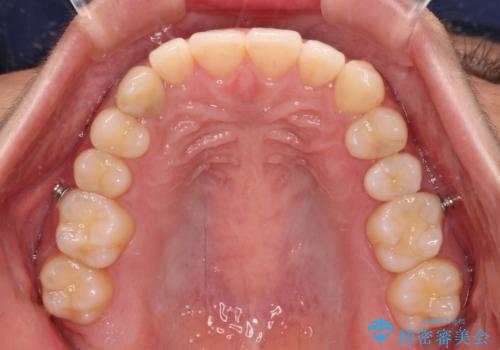

- 下顎の八重歯を気にして来院された患者様です。

マウスピース矯正でもワイヤー矯正でも対応可能であり、マウスピースによる治療を希望されたため、インビザラインを用いることとしました。

下顎前歯にデコボコが集中していたため、顎間ゴムによる後方移動とIPR(歯と歯の間を削ること)により歯列を整えることとしました。

しっかりとマウスピースを装着してくださったおかげで、スムーズに治療を終えることができました。

矯正治療途中で右下奥歯の虫歯治療を近医で行ったようで、既に神経が失活していたと合わせて矯正治療後に補綴治療を行う予定です。